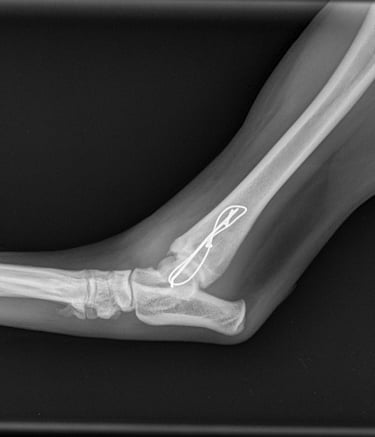

Orthogonal xrays reveal a lateral malleolus fracture (Fig.1 and 2), stress views and palpation revealed stable joint with no affection of collateral ligaments but due to the fracture there is some degree of rotational instability. Surgical stabilization is strongly advised as Buddy is a 40 kg patient.

Fig. 2

Fig. 1